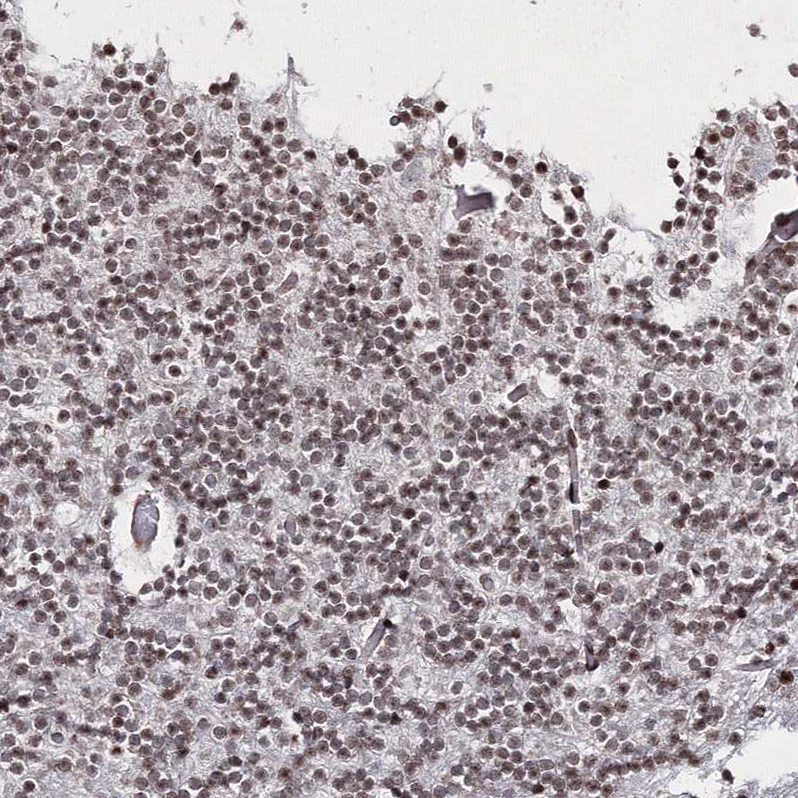

Immunohistochemical staining of human cerebral cortex shows strong nuclear positivity in neurons.